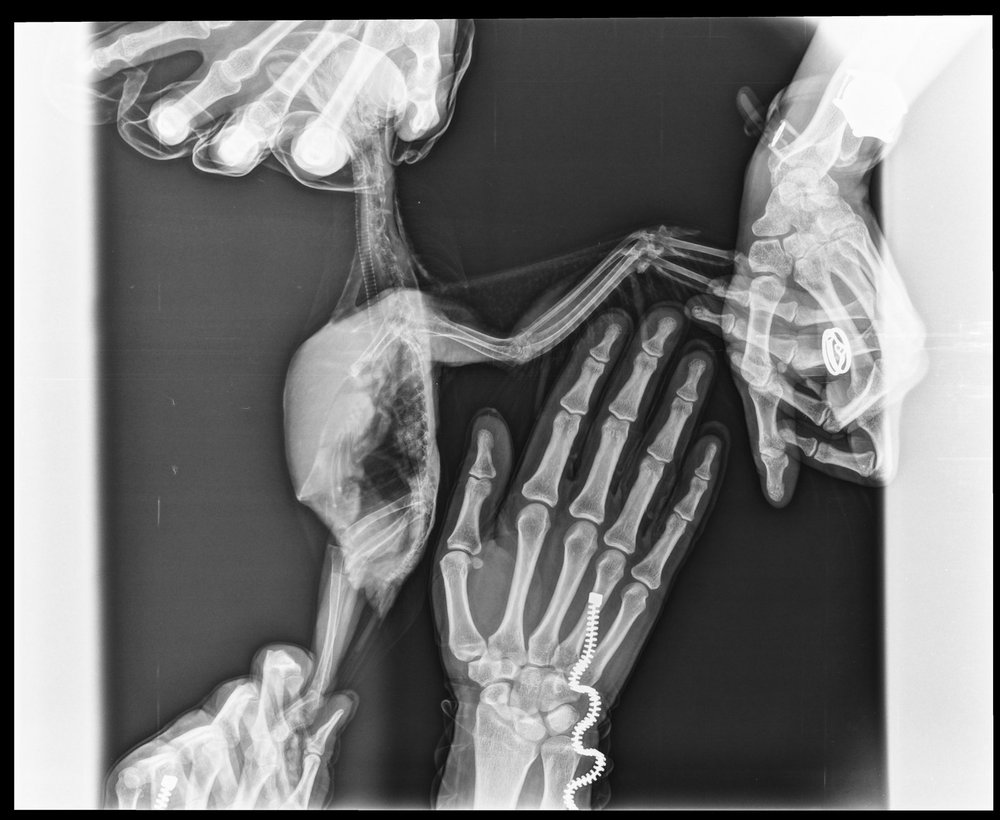

KamaRo Опубликовано 28 ноября, 2018 #8 Опубликовано 28 ноября, 2018 @Nadea про Аронову спросила, т.к. подумала, что она в декрете и сейчас прием не ведет. Аронова стажируется у Волгиной, что говорит о стремлении доктора постоянно расти. А с птицами всегда тяжело, много чего остается за нашим пониманием (не все виды исследований доступны, как у кошек/собак). Если вы у другого врача наблюдались, то о нем тоже хорошие отзывы не помешали, чтобы владельцев птиц направлять к специалисту. При сильном нарушении в работе органов, в т.ч. ЖКТ нужно препараты давать в клюв, с едой мало попадает по назначению. У вас и антибиотики были и довольно тяжелый для печени препарат - орунгал, поэтому лечить уже в комплексе нужно (и гепатопротекторы принимать, и про-пребиотики). Не плохо работают при нарушении микрофолоры - споровит+бифидо-и лактобактерии, фортифлора+бифидо-и лактобактерии, были не плохие результаты на энтероле+пробиотик. Просто какой то метод выбирают и дают в клюв. Споровит (в жидком виде) по 0,3 мл 2 раза в день, методом подбора лакто-и бифидосодержащий пробиотик (мне всегда нравился бифидумбактерин - там 5 доз, на волнушку на глаз флакон делила на 8 приемов, шпажкой откалывала, разводила водой и выпаивала), на амазона наверное 1/2 флакона на 2 приема (утро-вечер). Что касается гепатопроткторов, то их еще с месяц дают после противомикробных препаратов и тоже в клюв. Шрот расторопши в данном случае не особо помогут - это полезная добавка, но в качестве самостоятельного компонента не справится. Гептрал может быть на гепатовет заменить, но он жутко вонючий, но птицы его вполне не плохо переносят, особенно если на 2 приема разделить (но его нужно разводить, т..к суспензия густая и тяжело выпоить). Сейчас вам нужно восстанавливать птицу.